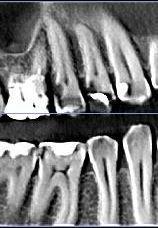

Интересовала в частности развалившаяся 6-ка сверху.

уже давно леченная -перелеченная.

Вердикт -надо кроме нее удалить также и 4 и 5 рядом стоящие - типа киста.

По поводу 6 ки я еще готов удалить так как там похоже невозможно что-то сделать но 4-ка с 5-кой свиду не такие плохие. возможно их перелечить ?

Отскринте нормально снимок: чтобы полностью было видно и корни зубов!

Добрый вечер, может опять не так сделал?

tecom, нормально! А вот на 4 и 5 кисты нет! Но лечить зубов очень много: практически каждый...

Плюс ещё пародонтит в том числе на 4 и 5...